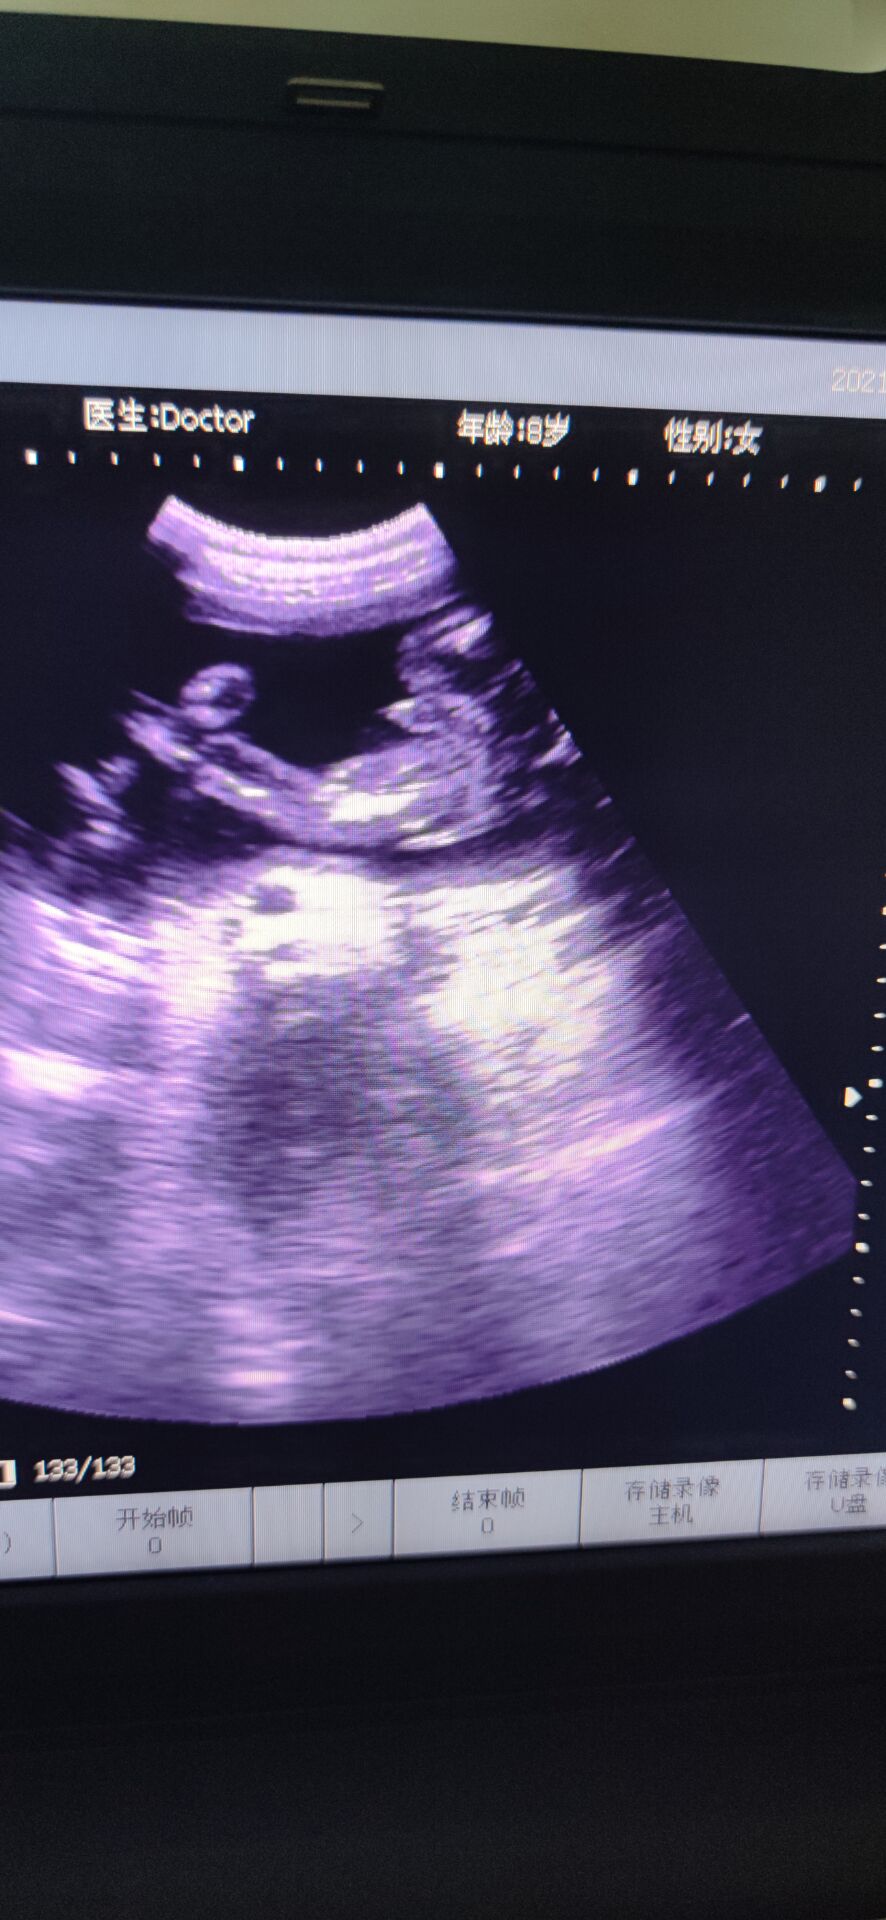

6月5日下午,分泌物有点血丝,而我在洗碗的时候,小腹有点点坠痛,但是休息下能缓解,到了晚上跟孕妇群的人聊了聊,不放心,挂急诊,B超做了好久,突然医生让我别动,就躺着,说:“你宫口已经开了,内宫口全开了,外宫口开了两指了,羊膜在阴道里,都快到阴道口了!”听到的那刻,突然就心慌紧张了,整个人都在发抖,腿也控制不住地抖,才26周啊,还没足月。产科的人立马下来把我拉到待产室内检,然后跟我说还没足月,什么都还没发育好,生下来就要立马进保温箱,要生下来起码得准备一百万…说了很多,大概意思都是劝我引产,可是我舍不得啊,我下不定决心,她们就破例让我老公进来,同样地话跟我老公说了一遍,但是我们想保,医生就给了建议,转入市人民医院,那里有紧急环扎术,当天晚上就转过去,中途医生给我上了抑制宫缩的药。转过去的时候已经是清晨两点多了,医生说她们医院已经不做紧急环扎术了,她也不知道哪个医院能做,而且这么晚了,我再转院也是折腾,我这才26周,产科和妇科不会收的,只能收计划生育科,但是计划生育科是不会管我的,因为我这情况医学上说就是难免流产,打完从上一个医院带来的吊瓶后,是不会管我的,顺其自然。这不是我们想要的答案,医生说没有其他办法,我们也不知道该怎么办,想着先转计划生育科吧,当晚做的核酸,但是因为核酸报告没那么快出,所以把我放到了抢救室,期间打了一枚促肺针。那晚好煎熬啊,睡又睡不着,周围都是打吊瓶的人,临急出的门,手机又没什么电,又不敢乱动,躺的身子僵硬疼痛,又不能下床走动,老公给我买了包护理垫,上厕所就直接尿在护理垫上。好不容易熬到早上,核酸报告还没出,到了十点多也没出,我老公在网上查资料,打电话,看哪个医院可以做紧急环扎,他侧对着我坐着,我看到他哭了,默默在流泪,那时候真心疼他。好不容易市妇幼说她们医院可以做,但是不派车来接,人民医院也不派车送。怎么办呢,叫出租车吗?可是出租车会愿意拉我吗而且我还得躺着。我老公和我家公就出去联系私人救护车。出去了好久,我就躺在床上望着门口,一有人进来,我就以为是他们回来了,但是不是,是别的病人的家属,后来我借别人手机给他打电话,我说:“你不要离开太久,我一个人在这,我害怕[泣不成声]”我老公他们好不容易联系到私人救护车把我送到市妇幼,内检时医生说做不了紧急环扎了,我已经有宫缩了,只能打吊瓶,抑制宫缩。因为疫情原因,只能一个陪护,我老公做的核酸还没出报告,要明天才能出,所以临时请了个月嫂陪护我,那天已经是6月6日了,晚上睡觉的时候感觉尿尿那里湿湿的,一擦,有血丝,而且不是一点点,叫了医生,医生给我上了另一种抑制宫缩的药,没一会就心跳加速,医生说那药是会让心跳加速,还让我如果有宫缩要告诉她。那一整晚都睡不安稳,一整晚,时间才过去五分钟,感觉太难熬了。等到6月7日中午,我老公的核酸报告出来了,他终于可以进来陪护了,心里开心了一些,做了B超,显示是26+6周,980克。因为我们要保,所以儿科医生也过来跟我们说了些关注事项和风险,还安慰我说,我这孕周和宝宝体重也还好,她们治疗过很多早产儿,百分之九十都能健康平安出院,让我不要太担心。